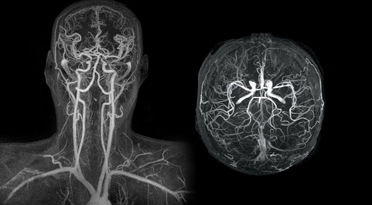

Магнитно-резонансная томография по сосудистой программе с контрастом позволяет тщательно изучить микроциркуляцию головного мозга, шеи, почек, аорты. Нативное сканирование применяется для выявления рассеянного склероза, болезни Альцгеймера, демиелинизации (разрушение миелина нервных оболочек), дегенеративно-дистрофических процессов.

Традиционная МРТ с сосудистой программой визуализирует артерии, вены, лимфатические сосуды, капиллярную сеть. Информация необходима для:

- Выявления участков сужения (окклюзий и стенозов);

- Образования соустьев между артериями и венами – мальформации;

- Диагностики трещин и расслоения стенки сосудов – аневризма;

- Обнаружения замедления кровотока из-за атеросклеротических бляшек;

- Верификации врожденных артериальных аномалий – патологические изгибы, деформация, гипоплазия.

Изучая фото МРТ сосудов мозга, специалисты выявляют тромбофлебиты, кровяные сгустки, атеросклеротические бляшки или неврологические сужения. Патология поверхностной мозговой венозной сети возникает редко и обусловлена недостаточностью клапанов.

Магнитно-резонансная томография позволяет провести обследование практически любого внутреннего органа и системы организма. МР-ангиография выполняется для сосудов мозга, шеи, сердца, позвоночника. В целом этот вид обследования подходит для сосудов любой локализации, где бы они не размещались — в брюшной полости или головном мозге. Он может проводиться с успехом даже на довольно слабом оборудовании - достоверные результаты можно получить на томографе с напряженностью магнитного поля от 0,3 Тл.

При МР-ангиографии делают внутривенное усиление препаратами гадолиния. Средство не токсично, быстро выводится почками, не вызывает аллергии. Для пространственного изучения анатомического объекта программное обеспечение создает трехмерную (3D) реконструкцию нужной области на основе полученных томограмм.

При подозрении на изменения мозга детям после рождения делают УЗИ. Пока роднички черепа не закрылись, врачи имеют возможность выявить патологию. Когда черепная коробка полностью покрывается костной тканью, только магнитно-резонансная томография верифицирует белое и серое вещество, выявляет кровоизлияния, оценивает микроциркуляцию Виллизиевого круга, венозных синусов, измеряет размеры субарахноидальных пространств.